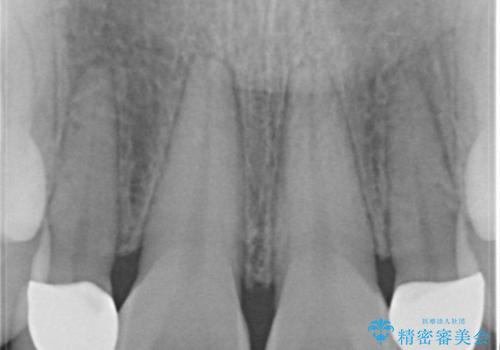

- 上の前歯が大きい事と下の前歯のがたつきを気にされてご相談にいらした方です。上の2番目の歯が矮小歯であったため、矯正治療にて歯のスペースを作った後、矮小歯には被せ物をして前歯のバランスを整えました。

歯科技工士さんとの打ち合わせを重ね、周囲の歯としっかりなじむ天然歯のような被せ物をお作りすることが出来ました。

矯正治療と補綴治療をうまく組み合わせることで、美しい口元に仕上げることが出来ました。矯正治療、補綴治療をまとめて行える総合歯科治療を体現した治療といえます。